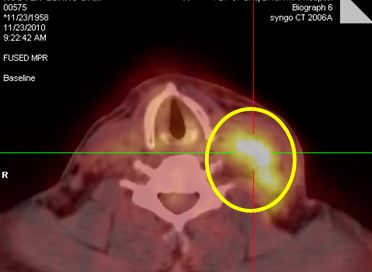

• Chụp PET/CT đánh giá toàn thân trước điều trị: Hình ảnh khối hạch vùng cổ trái kích thước 10x12 cm, tăng hấp thu FDG mạnh. Cơ quan bộ phận khác không thấy tăng hấp thu FDG.

• Hình 1: Hình ảnh khối hạch vùng cổ trái kích thước 10x12 cm, tăng hấp thu FDG mạnh (vòng tròn vàng).

Hình 4: Trước điều trị: Hình ảnh khối hạch vùng cổ trái kích thước 10x12 cm, tăng hấp thu FDG mạnh (vòng tròn vàng).